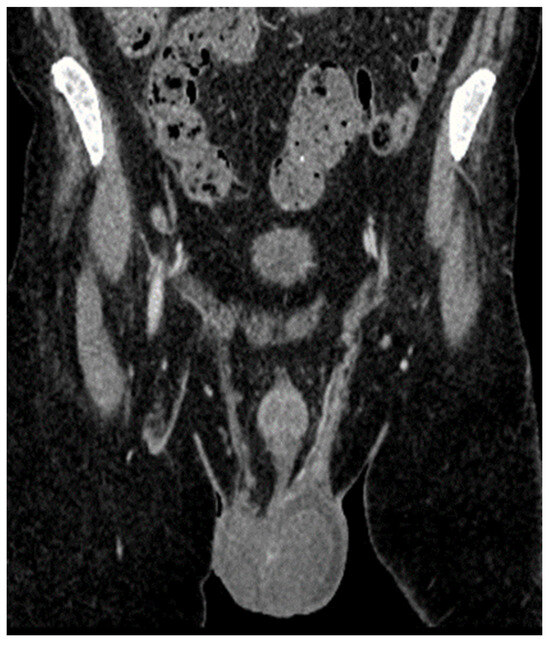

| 2 May 2023 | third emr: cardiac and colonic mass (+cns?) | nelarabine+cyclophosphamide+ etoposide |